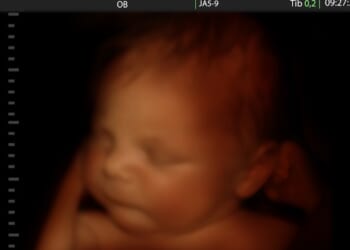

By Samantha Kamman, Christian Post Reporter Friday, November 28, 2025CraigRJD/iStockAdvocates are calling for action after dozens of pregnant women or their families alleged in a new report that jails in the United States…